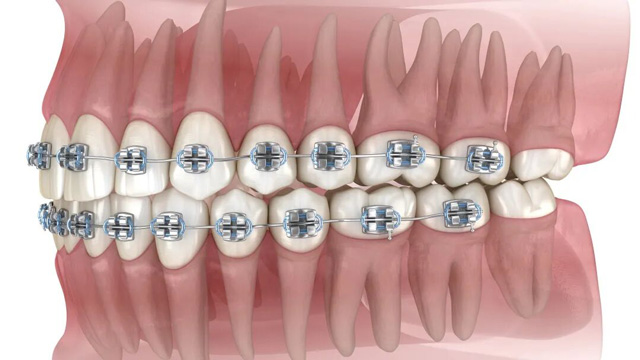

02智齿阻挡正畸牙齿移动

正畸治疗中,医生会根据诊疗方案,让牙齿沿着预设轨迹移动(比如前牙内收、后牙调整咬合等)。比如需要内收前牙改善凸嘴时,智齿的存在会“顶住”后牙,导致牙齿无法顺利移动到理想位置。这种情况,可能需要拔除智齿来为排齐牙齿提供必要的空间。